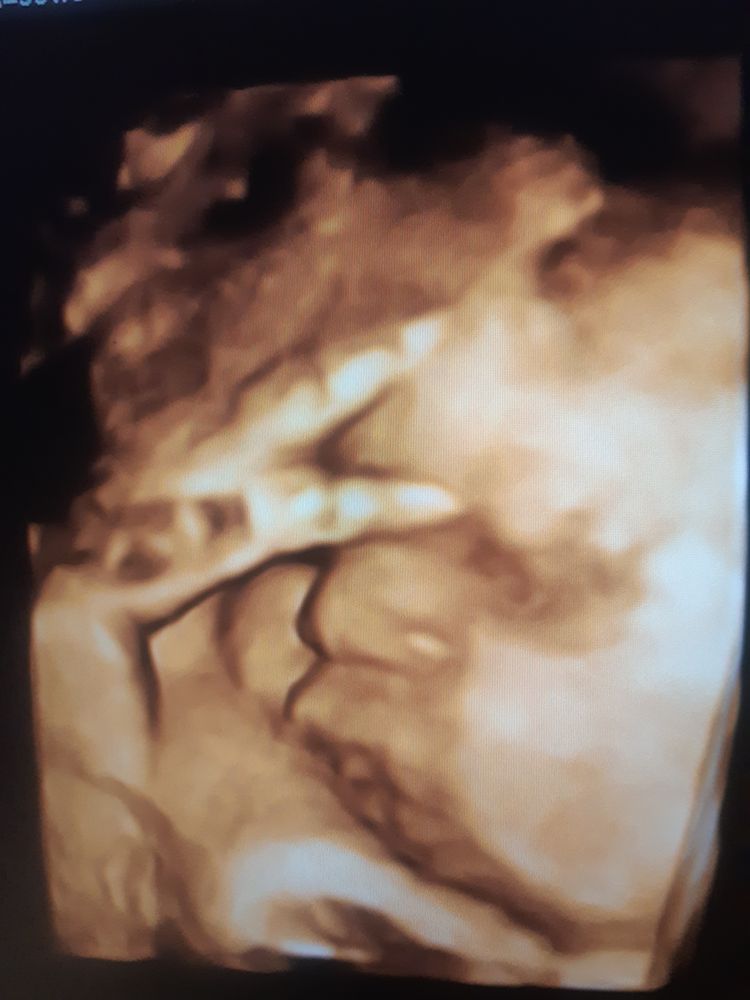

На память🥰🥰🥰

Затрудняюсь с категориейЗаканчивается 33 неделя Б)Что,хочу подчеркнуть ходить пешком стало,гораздо тяжелее.По вечерам,бывает изжога,что мало приятно и до Б не было)Сумка в роддом уже собрана,мне кажется набрала я мама не горюй,думаю половину с пачек повыкладывать,муж довезет)В жк в четверг была на ктг,сказали доча не особо активна...поехала в пятницу в перинаталку на 3 скрининг,сказали все отлично с доченькой,2 кг ровно))Осталось совсем немногоооо❤❤❤